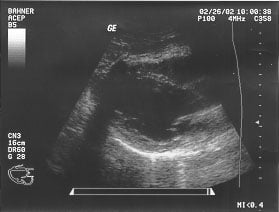

Cardiac - short axis parasternal - mid (unlabeled)